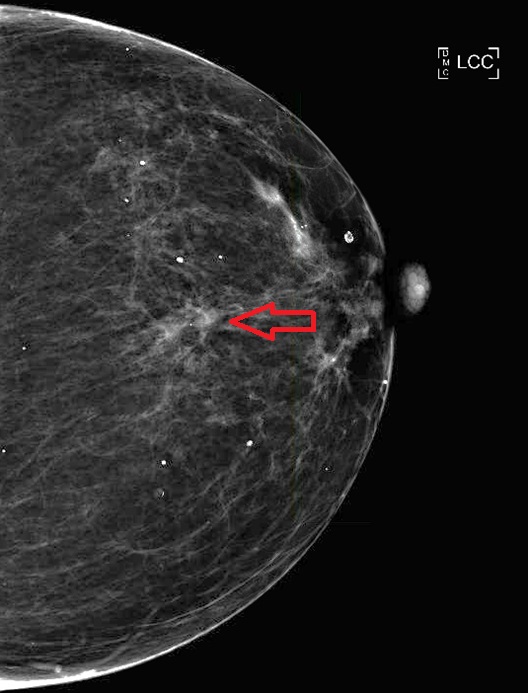

الحالة الأولى: تم اكتشاف كتلة في الثدي الأيسر. ثم تشخيصها بعد عمل خزعة بالأشعة التلفزيونية. تم عمل PET CT بعد ذلك واتضح وجود الكتلة وانتشار لأحد فقرات الظهر. ثم عمل ال MRI ويتضح وجود الكتلة في الجزء الخلفي الخارجي للثدي الأيسر.

تم علاج المريضة بعلاج اشعاعي لمنطقة الفقرة المصابة وعلاج السرطان بالعلاج الكيماوي واختفى بعد ذلك في الرنين المغناطيسي ثم تم استئصاله كاملا والحمدلله.

الحالة الأخيرة: كتلة صغيرة جدا في الثدي الأيسر. تم عمل رنين مغناطيسي واكتشاف انتشار للغدد اللمفاوية المجاورة. تم علاج المريضة واستئصال الكتلة والغدد بشكل كامل.